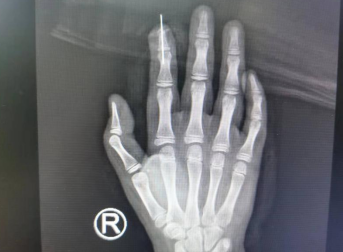

术前

很快,李海建医生医疗组为患儿进行了“右示指清创+骨折复位内固定+血管、神经、甲床撕脱皮肤修复术”。术中探查见右示指远节指骨骨折、指固有动脉、神经完全断裂,甲床断裂,首先对骨折断端进行复位内固定,接着在高倍显微镜下观察,寻找血管断端,进行细心吻接,手术顺利,一次通血成功,再植指体红润、毛细血管反应灵敏。

术后即刻